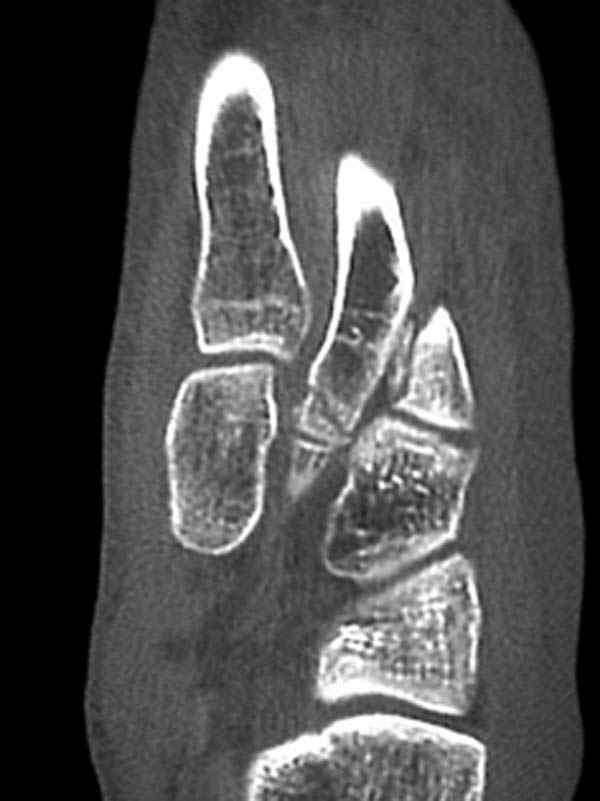

Здесь КТ и сравнительные снимки стопы под нагрузкой.

Диагностировано повреждение медиальной и латеральной колонны.